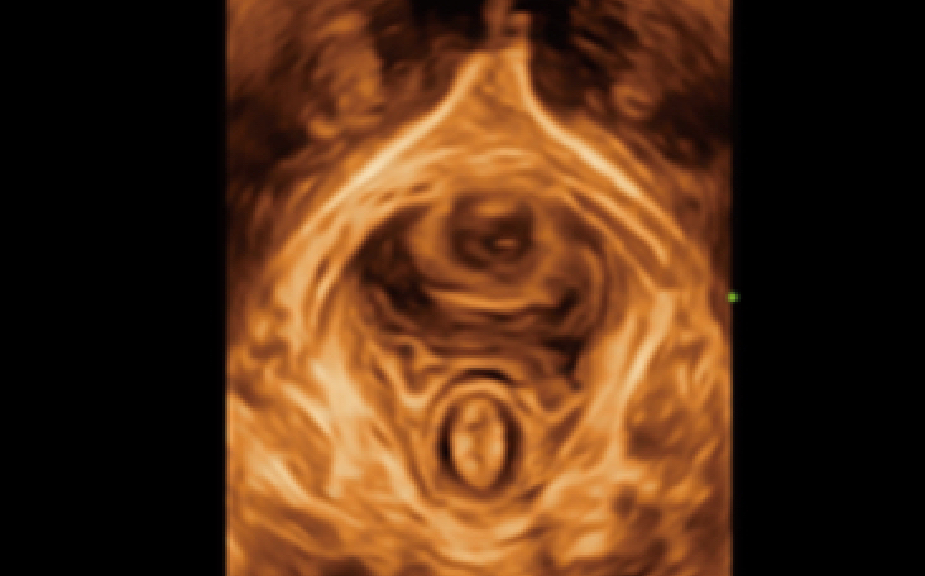

Innovative 2D Graf auto measurement

Graf method:

The most commonly used method for hip evaluation, the results correspond to a clear hip classification. The detection of key structures is based on deep learning algorithms. Automatic measurement (╬▒ and ╬▓) and classification.

Simple and Efficient:

Greatly improve the exam efficiency by simply one click.

Accurate and Reliable:

The system will judge whether the section is standard or not before calculation, and manual adjustment is also allowed.

Image acquisition